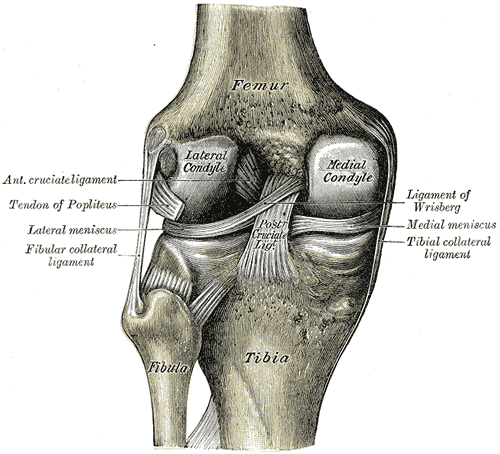

Rupturas dos ligamentos do joelho

Os ligamentos colateral medial (LCM) e colateral lateral (LCL), são as estruturas mais frequentemente lesadas no joelho. Na verdade, a ruptura parcial do LCM é a lesão ligamentar mais comum no joelho.

O LCM tem origem no epicôndilo femoral medial e na cápsula articular medial e insere-se na face medial da tíbia, e no menisco medial. Este ligamento é responsável por evitar movimentos excessivos em valgo do joelho

O LCL é um ligamento redondo que tem origem no epicôndilo lateral, logo abaixo do tendão do músculo bicípite femoral e se insere na cabeça do perónio. Este ligamento é responsável por evitar movimentos excessivos em varo do joelho